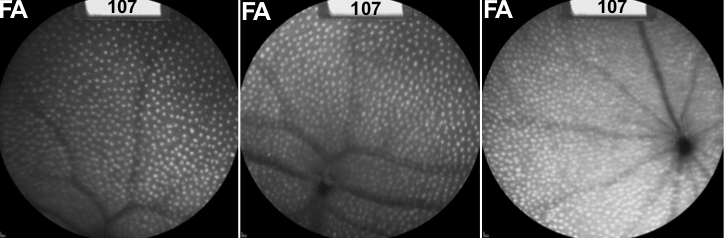

Hyperopia (farsightedness) is a common and significant cause of visual impairment and MFRP mutations can cause extreme inherited hyperopia (termed nanophthalmos). Exreme hyperopia leads to other significant visual comorbidities, such as angle closure glaucoma, cystic macular edema, and exudative retinal detachment. The Mfrprd6/Mfrprd6 mouse is used as a pre-clinical animal model of retinal degeneration, and we found it was also hyperopic. Our lab used AAV gene therapy to restore Mfrp function in these mice. The rescue was evaluated using non-invasive, human clinical testing, including fundus auto-fluorescence, optical coherence tomography, electroretinography, and ultrasound as well as through proteomic analysis of the mouse RPE.